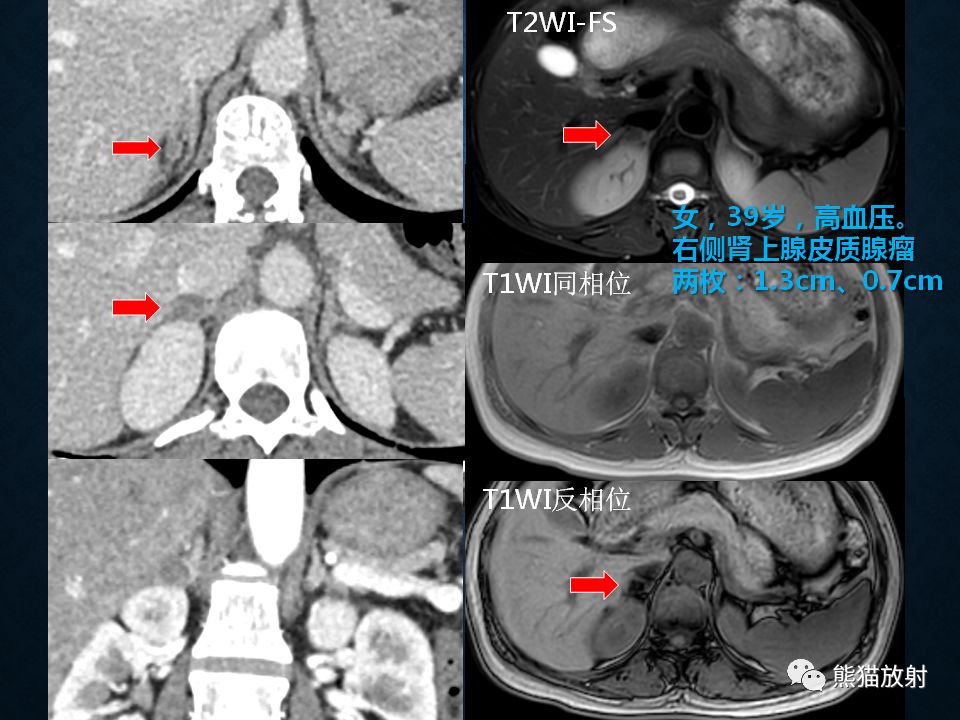

肾上腺常见肿瘤影像诊断

>腺瘤:临床表现决定于肿瘤的发生年龄,与 Cushing腺瘤表现相同,但无对侧萎缩改变

>皮质癌:约占30%

>先天性肾上腺增生:双侧肾上腺腺体显著弥漫性增大,程度常明显超过 Cushing综合征的皮质增生